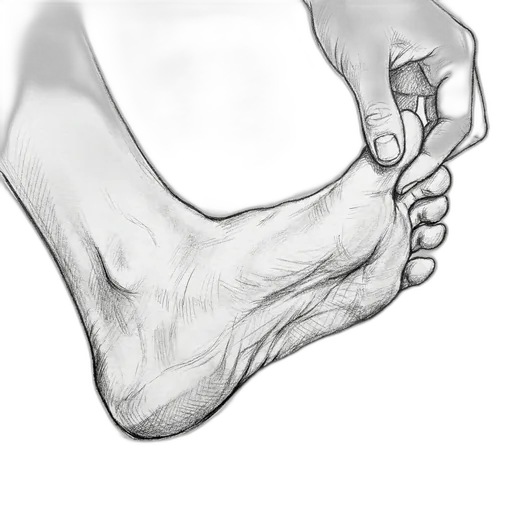

Hammertoe

At a glance: A hammertoe is a contracture (permanent bend) of the small joints of the toes, most commonly the second toe. In the flexible stage, you can still straighten the toe by hand — and that's when exercises make the biggest difference. Once the joint becomes rigid, the deformity is fixed and typically needs surgical correction. The exercises here target the intrinsic foot muscles that extend the toes and counterbalance the flexor pull that causes the curling.

Understanding Hammertoe

The small toes work through a tug-of-war between the muscles on top of the foot (extensors) and the muscles underneath (flexors), coordinated by the small intrinsic muscles inside the foot. When the intrinsic muscles weaken — from wearing tight shoes, neurological conditions, or simply from years of disuse — the flexors win and the toes buckle at the proximal interphalangeal (PIP) joint. This creates a raised joint that rubs against the top of the shoe, forming a painful corn. Over time, the tendons and joint capsule tighten, and the flexible deformity becomes rigid. Hammertoes frequently accompany bunions because the big toe drifting sideways crowds the second toe upward.

While the toe is still flexible, you have the best chance at managing it without surgery. If the toe has become rigid, if a corn is becoming ulcerated, or if the deformity is worsening, see Dr. Patish. He performs minimally invasive hammertoe correction — a small puncture incision, local anesthesia, and you walk out the same day in a surgical shoe.